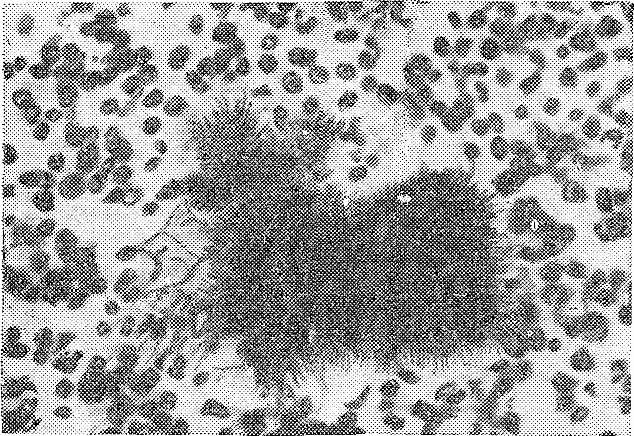

Непосредственно актиномикоз (actinomycosis) вызывает Аctinomyces israelii, реже A. naeslundii/viscosus, A. odontolyticus, A. meyeri и A. gerencseriae[6]. Актиномикоз может поражать кроме лёгких и другие органы и ткани человека: щитовидную железу, кожу, почки и др. В патологическом материале колонии грибов встречаются в виде так называемых друз, которые представляют собой желтоватые комочки диаметром 1-2 мм.

При внедрении возбудителей образуется инфекционная гранулёма, которая в последствии прорастает в окружающие ткани. В центре гранулёмы происходят некроз клеток и их распад, возникают абсцессы, которые, прорываясь, образуют свищи[7]. Для данной болезни характерна интоксикация и бронхит, образование полостей распада сопровождается мучительным кашлем, выделением гнойной мокроты, кровохарканьем[8].